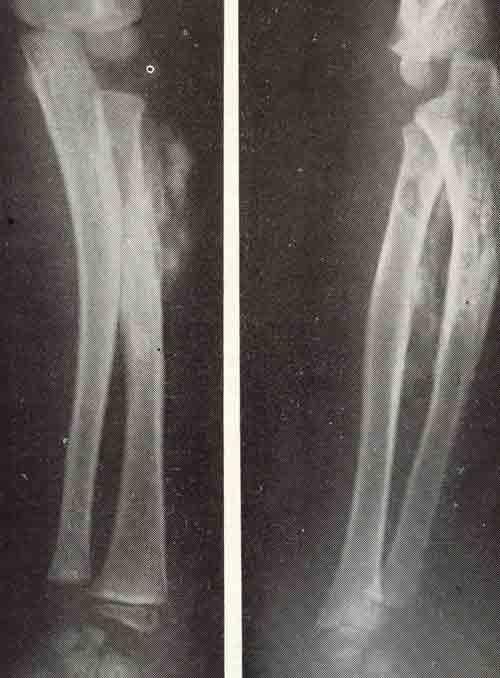

В дифференциальной диагностике костных поражений следует иметь в виду особенности травмы и регенерации растущей кости. Известна активная реакция надкостницы при повреждении костей у детей. Избыточная костная мозоль может симулировать опухоль при обычном переломе бедренной кости у маленького ребенка.

Костная мозоль

Костная мозоль после обычного перелома бедра у новорожденного

ребенка, симулировавшая саркому.